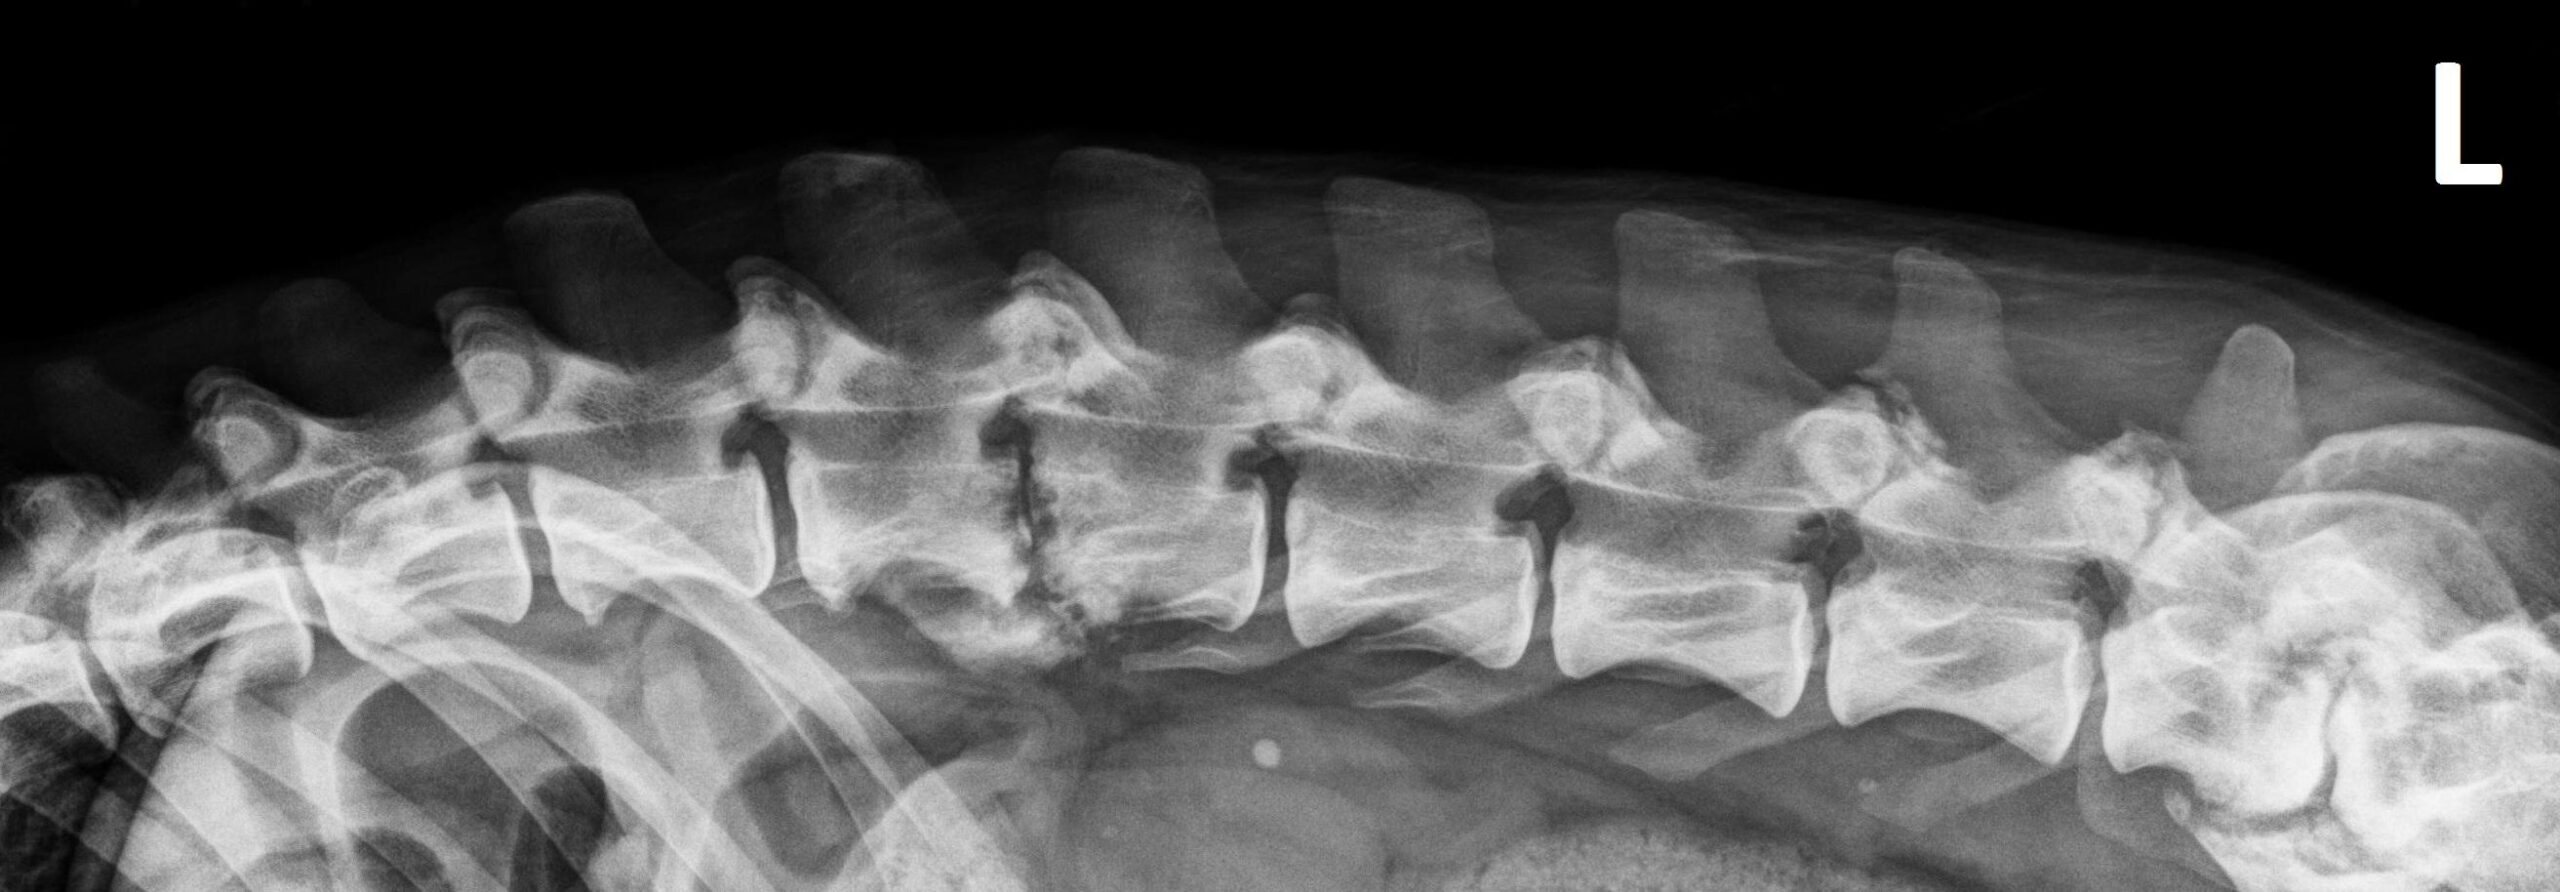

Orthogonale opnamen van de lumbale wervelkolom zijn beschikbaar voor interpretatie.

Er is een uitgesproken onregelmatigheid van de caudale eindplaat van L2 en de craniale eindplaat van L3, met vernauwing van de tussenwervelschijf L2-L3 en matige spondylosis deformans op dit niveau.

Er is multifocale verbreding van de lumbale facetgewrichten met onregelmatige peri-articulaire botnieuwvorming.

Er is vernauwing van de tussenwervelschijf L7-S1 met sclerose van de aangrenzende eindplaten en spondylosis deformans op dit niveau.

Lichte spondylosis deformans wordt opgemerkt ter hoogte van bijkomende lumbale tussenwervelschijven.

Een goed afgelijnde, ronde, mineraal-dense structuur wordt waargenomen in de linker nier.